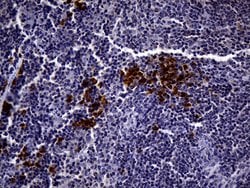

CD3 Mouse anti-Human, Clone: UMAB54, liquid, UltraMAB™

Mouse Monoclonal Antibody

Brand: Origene Technologies UM500048

CD3 epsilon is part of the CD3 subunit complex which is crucial in transducing antigen-recognition signals into the cytoplasm of T cells and in regulating the cell surface expression of the TCR complex. T cell activation through the antigen receptor (TCR) involves the cytoplasmic tails of the CD3 subunits CD3 gamma, CD3 delta, CD3 epsilon and CD3 zeta. These CD3 subunits are structurally related members of the immunoglobulins super family encoded by closely linked genes on human chromosome 11. The CD3 components have long cytoplasmic tails that associate with cytoplasmic signal transduction molecules and this association is mediated at least in part by a double tyrosine-based motif present in a single copy in the CD3 subunits. CD3 may play a role in TCR-induced growth arrest, cell survival and proliferation. The CD3 antigen is present on 68-82% of normal peripheral blood lymphocytes, 65-85% of thymocytes and Purkinje cells in the cerebellum. It is never expressed on B or NK cells. Decreased percentages of T lymphocytes may be observed in some autoimmune diseases. The genes encoding the CD3 epsilon, gamma and delta polypeptides are located on chromosome 11. Defects in this gene are associated with T cell immunodeficiency and has been linked to Type 1 Diabetes deficiency in women.Specifications

| Immunocytochemistry, Immunofluorescence, Immunohistochemistry (Paraffin) | |

| UMAB54 | |

| Full length human recombit protein of human CD3E produced in HEK293T cell. | |